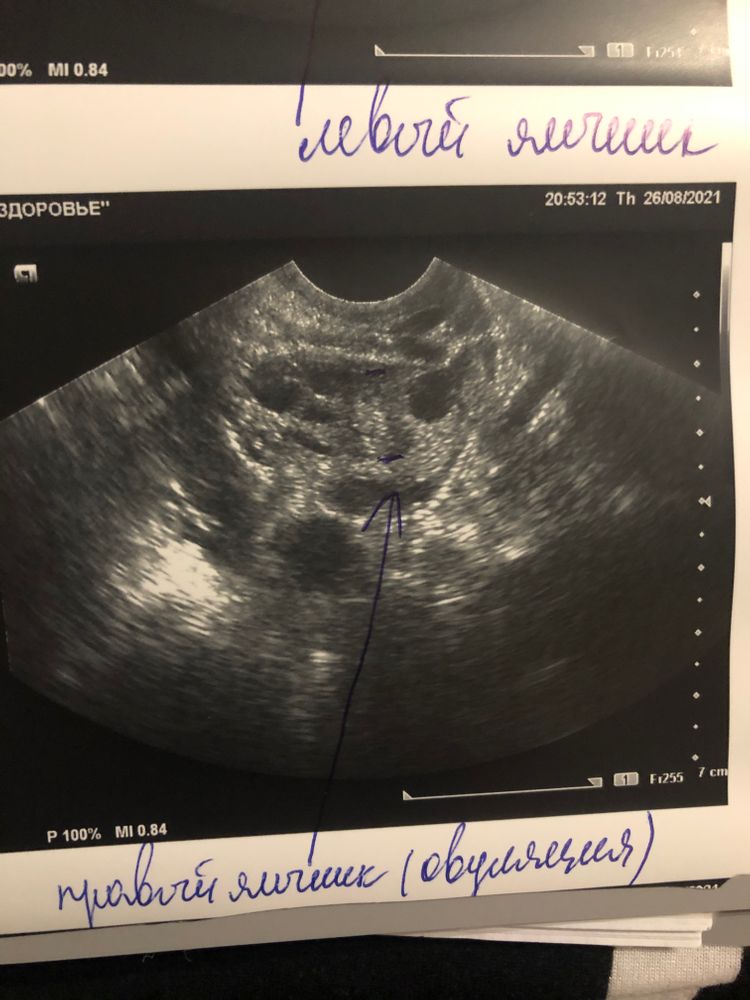

Там где написано «левый яичник (овуляция)» и стрелочка к формирующемуся жт. У меня такое же жт было ещё маленькое, когда я приходила в день овуляции. А в правом яичнике у вас ДФ

Евгения, не эт все в правый яичник, там написана правый. Эт в разные дни цикла.получается вы видите жт?

Tina, да, опечатались просто. У вас ЖТ в стадии формирования. Получается, что когда яйцеклетка выходит из фолликула, то он сдувается сначала, а через несколько часов ЖТ уже начинает увеличиваться в размерах. Если что это не моя фантазия, это мне Г так объясняла, потому что я однажды пришла на узи точно с такой же картиной)

Так вот же, увидела ! 26.08, правый яичник, овуляция!!! Так что считайте ДПО!